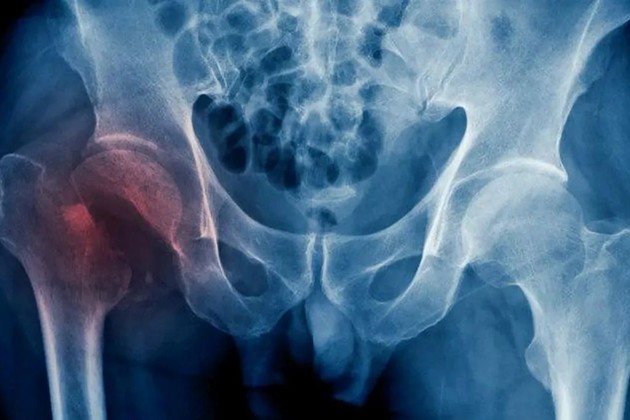

Según explicó, estas fracturas se suelen dar normalmente en cuatro zonas y generan las denominadas “fracturas por fragilidad”: la cadera, la columna, la muñeca (radio distal) y el hombro (húmero proximal) que, ante traumas mínimos en un paciente con osteoporosis, pueden generar fracturas.

La osteoporosis del anciano suele ocasionar fracturas de huesos largos, en su mayoría el fémur, siendo responsable de las típicas fracturas de cadera.